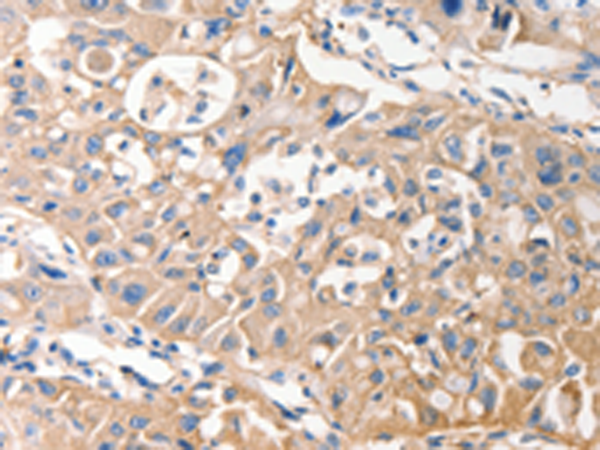

IHC positive control: |

Human lung cancer and Human esophagus cancer |

IHC Recommend dilution: |

25-100 |